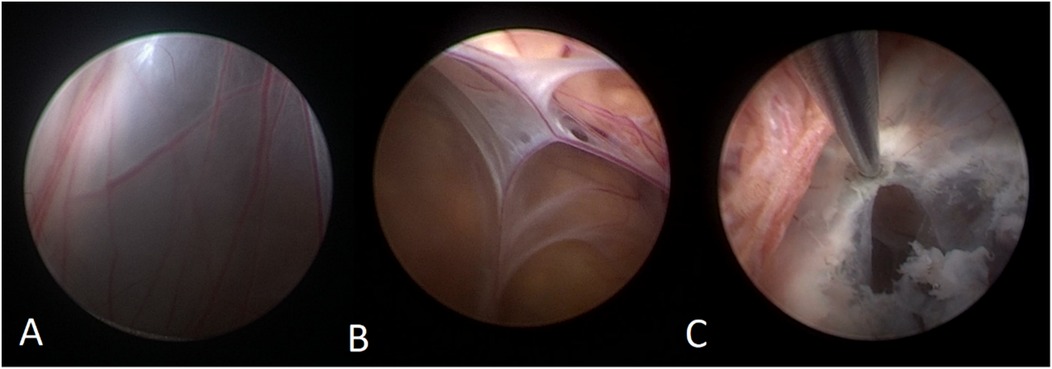

A 50-year-old male patient was admitted with a complaint of a persistent headache lasting for three hours. His medical history was notable for a 20-year history of smoking, with no evidence of hypertension or diabetes. Upon physical examination, the patient was found to be alert and oriented, with a Glasgow Coma Scale (GCS) score of 15 (E4V5M6). The pupils were bilaterally isocoric at 3.0 mm and exhibited intact light reflexes. Signs of meningeal irritation were absent, and no significant neurological deficits were detected. Cranial computed tomography (CT) and computed tomography angiography (CTA) revealed a subarachnoid hemorrhage and an aneurysm of the left internal carotid artery at the ophthalmic segment (Figures 1A,B). He was classified as Hunt-Hess grade II and modified Fisher grade III. The patient underwent a craniotomy for aneurysm clipping. The initial postoperative CT scan of the head demonstrated post-clipping alterations and a marked reduction in the intracranial hematoma relative to prior imaging (Figure 1C). Following this, the patient was administered continuous lumbar drainage of hemorrhagic cerebrospinal fluid (CSF) in conjunction with appropriate supportive care. Three weeks postoperatively, the patient demonstrated a favorable recovery and was discharged without complications. However, 10 days after discharge, the patient was readmitted in a state of sudden coma. The left pupil was noted to be dilated with an absent light reflex. An emergency cranial CT scan revealed the formation of a hematoma in the left frontotemporal lobe, indicating the possibility of rebleeding at the surgical site (Figure 1D), the patient underwent an emergency craniotomy for the evacuation of a hematoma. Intraoperative exploration revealed a recurrent and reruptured aneurysm located in the ophthalmic segment. Successful aneurysm clipping was achieved, along with hematoma evacuation and decompressive craniectomy (Figure 1E). The procedure was completed without complications. After an uncomplicated clinical recovery, the patient was discharged. The pre-discharge follow-up cranial CT scan showed postoperative changes in the brain, with no other significant abnormal findings observed (Figure 1F). Fifteen days post-discharge, the patient exhibited cognitive decline and left-sided weakness. A readmission cranial CT scan revealed a cystic lesion located dorsal to the right ambiens cistern and medial to the parahippocampal gyrus (Figure 2A). Serial imaging conducted at a three-month interval demonstrated progressive enlargement of the cystic lesion (Figure 2B). Subsequent cranial magnetic resonance imaging (MRI) excluded the presence of gliomas and cholesteatomas (Figures 2C,D). One year later, amidst ongoing neurological deterioration, follow-up cranial CT indicated further expansion of the cystic lesion, accompanied by a significant mass effect (Figures 3A,B). Neuroendoscopic exploration was conducted under general anesthesia, during which a cortical fenestration of the temporal lobe was created to facilitate access to the cystic cavity. Intraoperative observations revealed a thickened cyst wall under high tension with evidence of vascular proliferation. The cystic fluid was colorless and transparent, lacking hemosiderin deposition (Figures 4A–C). An arachnoid cyst was suspected intraoperatively, prompting partial resection of the cyst wall and the creation of a lateral ventriculostomy. The fistulous opening measured approximately 2.5 cm in diameter, facilitating communication with the lateral ventricle (Figure 4C). Histopathological analysis of the cyst wall confirmed the diagnosis of an arachnoid cyst (Figure 5). Following the surgical procedure, the patient demonstrated a gradual enhancement in left-sided motor weakness and cognitive abilities. At the three-month follow-up, both motor and cognitive functions had nearly returned to baseline levels. The GCS score was recorded at 15 (E4V5M6). The latest cranial MRI revealed a substantial reduction in cyst volume, accompanied by a complete resolution of the mass effect (Figures 3C,D).

Figure 4. (A) The neuroendoscopic image illustrates vascular hyperplasia within the cyst wall, accompanied by tension in the cyst wall. (B) The internal perspective reveals that the cyst is closely adherent to the cerebral ventricular wall, with blood vessels situated between the arachnoid membranes. (C) The thick-walled cyst is positioned adjacent to the choroid plexus, and it exhibited a reduction in size following cauterization of the cyst wall.

A neuroendoscopic evaluation of the arachnoid cyst revealed a bilaminar arachnoid wall characterized by intervening vascular proliferation. The cyst maintained its structural integrity under tension and was situated adjacent to the choroid plexus and the medial wall of the lateral ventricle, with no observable slit-like formations. The cystic fluid was colorless and transparent, resembling CSF, and comparative analysis confirmed its biochemical similarity to CSF. Immunohistochemical analysis demonstrated immunopositivity for epithelial membrane antigen (EMA). Definitive histological examination confirmed a fibrotic cyst wall devoid of epithelial cellular components. In this case, we propose that cyst enlargement may not primarily involve ball-valve mechanisms or osmotic gradients. Instead, it is plausible that unrestricted communication between the cyst and the subarachnoid space facilitates the transmission of CSF pulsations into the cyst cavity, or that active fluid secretion by the cyst wall itself may contribute to the expansion. Additionally, intraoperative observations suggest that the pronounced vascular proliferation within the cyst wall may expedite this enlargement process.